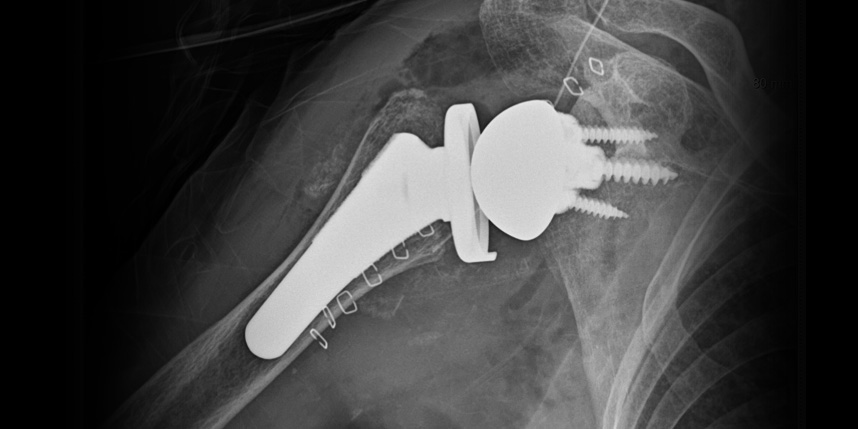

삼하게 망가져 거의 기능이 없는 관절을 제거한 후 특수하게 제작된 인공관절을 삽입하는 수술

역행성 인공관절 전치환술

역행성 인공관절 진치환술

(회전근개 심한 파열 및 관절염 진행)